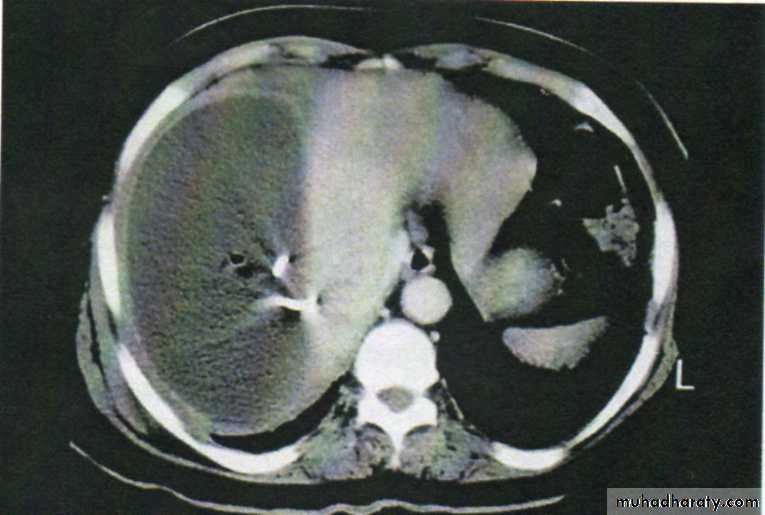

A swinging pyrexia is usually present. If the abscess is anterior, abdominal examination will reveal some tenderness, rigidity or even a palpable swelling. Sometimes the liver is displaced downwards but more often it is fixed by adhesions. Examination of the chest is important and, in the majority of cases, collapse of the lung or evidence of basal effusion or even an empyema is found.Investigations

• A plain radiograph sometimes demonstrates the presence of gas or a pleural effusion. On screening, the diaphragm is often seen to be elevated (so called “tented” diaphragm) and its movements impaired.

• Ultrasound or CT scanning is the investingation of choice and permits early detection of subphrenic collections